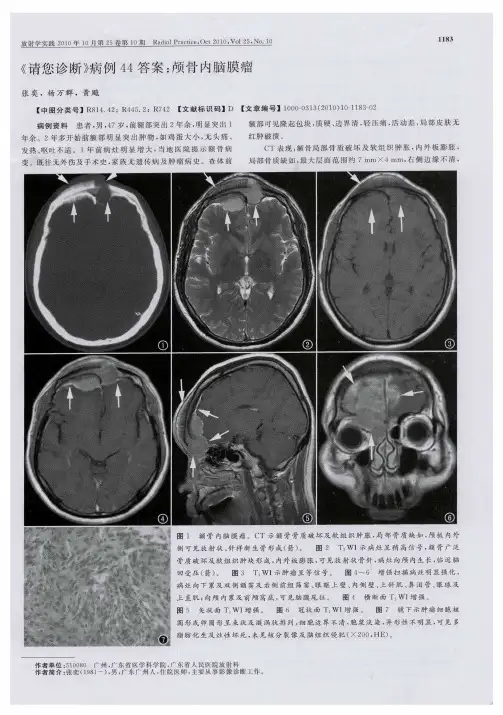

颅内肿瘤病例分析1. 病例背景本报告旨在分析一起颅内肿瘤病例,患者男性,45岁。

患者出现头痛、恶心、呕吐等症状,就诊时发现颅内压增高。

经过影像学检查和病理学诊断,证实为颅内肿瘤。

2. 病例分析2.1 症状分析患者出现头痛、恶心、呕吐等症状,提示颅内压增高。

这些症状可能与肿瘤的生长速度、位置和体积有关。

颅内压增高可能导致脑组织受压,引起头痛;同时,刺激呕吐中枢,导致恶心、呕吐。

2.2 影像学检查通过CT、MRI等影像学检查,可以观察到颅内肿瘤的大小、形态、位置和与周围组织的关系。

本病例中,影像学检查显示肿瘤位于大脑右侧,呈均匀增强,边界清楚。

这些特征有助于初步判断肿瘤的性质。